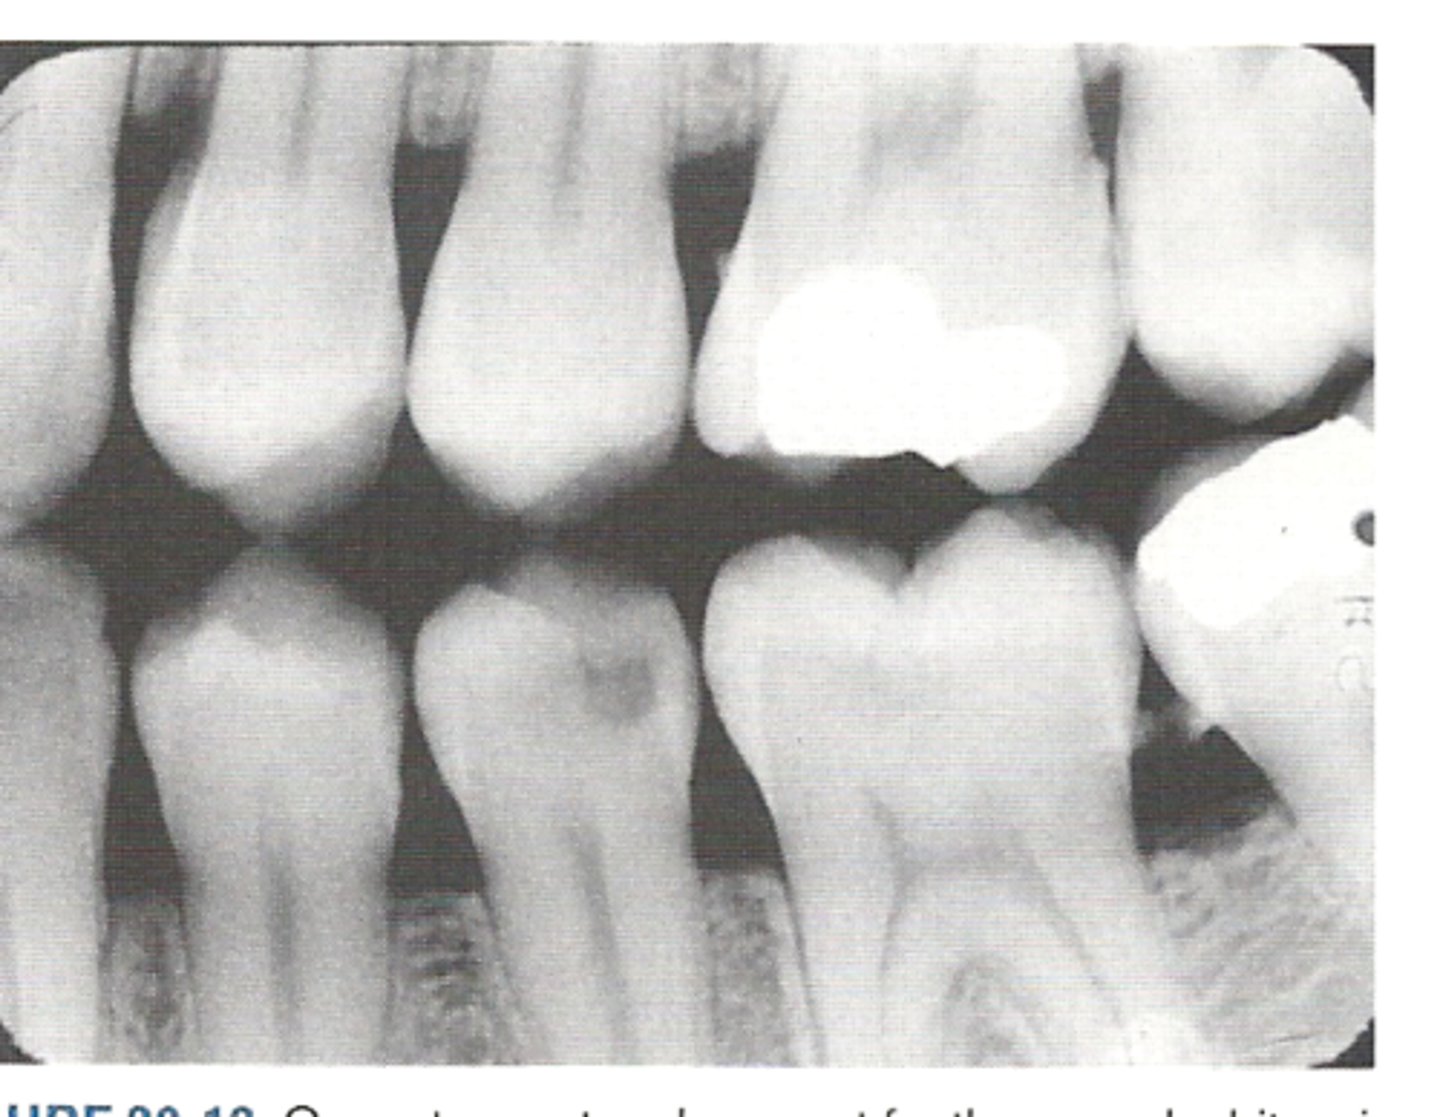

Bitewing

What type of x-ray is this?

What does a bitewing x-ray show?

the crowns of both the maxillary and mandibular teeth on a single image, along with the crestal bone

What is the primary purpose of a bitewing x-ray?

TO DETECT INTERPROXIMAL CARIES

What are some other purposes of a bitewing X-ray?

- monitoring CRESTAL BONE LEVELS/early signs of gum disease & periodontal disease

- checking the fit of existing restorations like crowns or fillings

What is the purpose of a horizontal bitewing?

It is the standard x-Ray for general cavity/bone checks; shows broad contact

What is the purpose of a vertical bitewing?

best for showing periodontal disease, revealing bone loss, root issues, or deeper decay